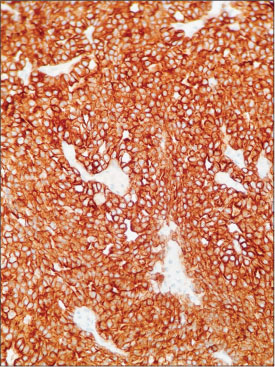

A 50-year-old male presented with two rapidly enlarging tender nodules on the scalp and distal finger of the hand. On physical examination, they were crusted erythematous nodules with focal areas of alopecia on the scalp. Multiple other cutaneous and subcutaneous nodules were evident on the right and left hand and left foot and calf. [Figure 1], [2], [3], [4] show the cutaneous nodules on scalp, both hands, and left foot and calf on further examination of the patient. Core biopsies of the scalp and hand nodules were sent for histopathological examination (HPE). Hematoxylin and eosin (H and E) stained sections showed tumor cells arranged in a lobular, microcystic, and acinar pattern. [Figure 5] and [6] show the low power and high power view (?10 and ?40, respectively), of round to polygonal tumor cells with basophilic granular to clear cytoplasm, and hyperchromatic nucleus and an inconspicuous to single nucleoli. Acini were comprised of cuboidal cells with clear to vacuolated cytoplasm showing PAS-positive cytoplasmic granules and pleomorphic, hyperchromatic nuclei with frequent atypical mitosis. A diagnosis of low-grade metastatic carcinoma was offered. The primary sites under consideration were the salivary gland, kidney, GIT, and the thyroid gland. Immunohistochemistry (IHC) revealed positive staining for AE1/AE3 [Figure 7], CK7, and DOG1 [Figure 8] and were negative for CK20, vimentin [Figure 9], p63, CDX2, CEA, TTF, PAX8, and S100. PAX8-negative immunostaining ruled out thyroid and renal origin of the metastatic tumor. CK7 positivity and CK20 negativity favored salivary gland origin. p63-negative staining ruled out myoepithelial salivary gland tumor. Further, DOG1 membranous and cytoplasmic positivity and P63 negativity favored ACC. The patient was reexamined clinically after the pathological diagnosis, and a preauricular scar was noted on the patient?s face, confirming a prior parotid surgery 20 years back. Thus, with a history of a previous surgery in the parotid region, HPE and IHC, a diagnosis of metastatic ACC was offered.

|?Figure. 8? DOG1 positivity

ACC is an uncommon salivary gland tumor. Among the salivary glands, parotid gland is most commonly affected. A single case report with widespread cutaneous metastasis has been reported.[3] In spite of being a low-grade malignant tumor, ACC has a propensity for late recurrence and metastasis, often many years after initial presentation. Most common sites of metastasis are the lungs, brain, and lymph nodes.[4] Case reports of isolated concurrent cutaneous involvement have been reported.[5] [6] Miki?et al. have suggested a minimum 10-year follow-up for patients with ACC in view of its propensity for late recurrences.[7] According to the World Health Organization classification, ACC is a malignant epithelial neoplasm of the salivary gland in which, at least some of the neoplastic cells demonstrate serous acinar cell differentiation, characterized by cytoplasmic zymogen secretory granules. Histomorphologically, ACC can display various growth patterns such as solid, microcystic, papillary, cystic, follicular, or various combinations of the above. Tumor cells in ACC usually resemble the serous acinar cells which are round to polygonal. The cytoplasm is fine or coarsely granular or may be clear. Cytoplasmic zymogen granules are the key to diagnosis which are positive to special stains such as PAS. Nucleus is eccentric with inconspicuous nucleoli. IHC shows focal positive or negative CK7 staining. Recent studies show that DOG1 is a promising marker in the diagnosis of ACC. DOG1 positivity and p63 negativity show 93%?100% sensitivity in the diagnosis of ACC.[8] [9]